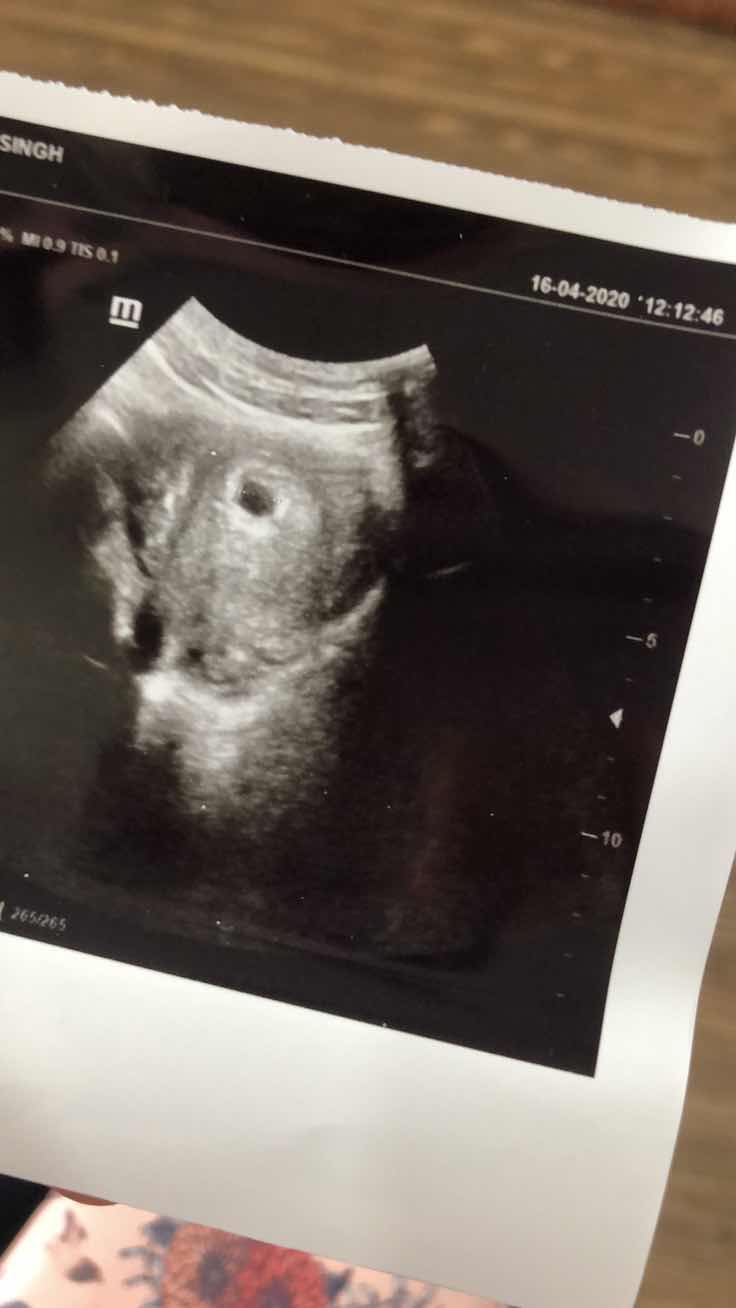

Masa check ni kalau ikut apps usianya dah nak masuk 6 minggu tapi scan doktor ckp baru nak masuk 5 minggu. Lambat seminggu, takpelah janji kesihatan kandungan tu yang penting. Bila tengok ada kantung tu mcm tak percaya. in shaa Allah dengan izin Allah semoga semuanya selamat sihat cukup sifat dari dalam kandungan sehingga lepas bersalin dan sehingga besar hendaknya Amin. Semoga selamat dan sejahtera ya semua ibu ibu terutama yang bakal menjadi ibu buat pertama kalinya seperti saya.